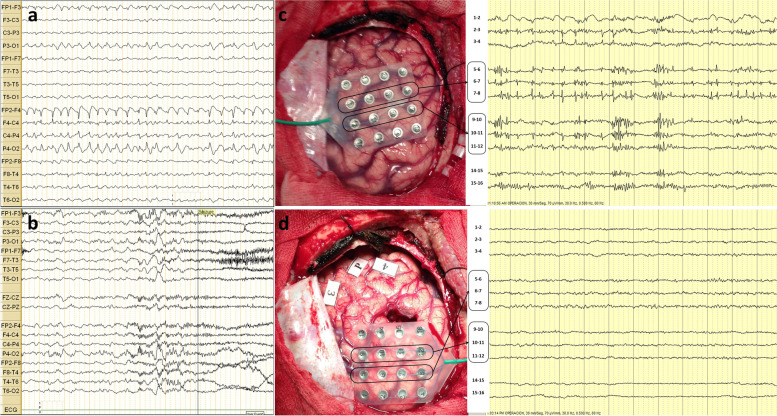

Case presentation: We report the case of a 21-year-old female with seizure onset at the age of 9, characterized by left-hand dystonic posturing and impaired awareness, which evolved to bilateral tonic-clonic seizures, evaluated in a neurological referral center in Lima, Peru. During 6-h video-EEG, interictal EEG revealing focal brief potentially ictal rhythmic discharges (BIRDs) over the right frontal central region, lasting less than 10 s. The ictal features were characterized by low-voltage fast activity over the same area. Brain magnetic resonance imaging (MRI) demonstrated a focal lesion of focal cortical dysplasia type II in the right frontal lobe. The patient underwent a lesionectomy guided by electrocorticography, which showed continuous polyspikes. BIRDs showing a brief burst of spikes lasting longer than 0.5 s, were also identified on intraoperative electrocorticography (ECoG) and helped define the extent of resection. The patient obtained an Engel Outcome Class IA at 6 years of follow-up.

Conclusions: The atypical BIRDs on ECoG can be used as a prognostic biomarker for prolonged seizure-freedom outcome in patients with epilepsy. Additional reports are needed in developing countries with and without brain MRI lesions to advance outpatient presurgical evaluations despite limited resources.